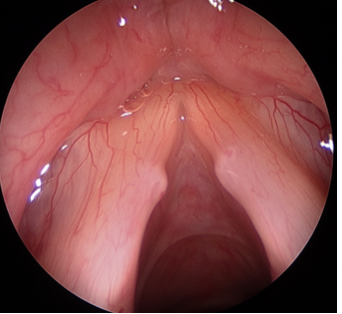

Наиболее частой причиной нарушения голоса у детей являются узелки. Они представляют собой узелки симметричной формы, которые возникают в передних частях обеих голосовых связок. Во время речи, они предотвращают голосовые связки от полного закрытия и качество звука ухудшается таким образом. Лечение узелков, в первую очередь, заключаться в гигиене голоса, звуковой и поведенческой терапии (для исправления речевых привычек необходимо обеспечить целостность терапии, включая психотерапию).